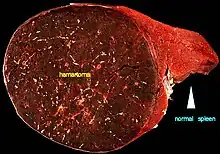

| A large hamartoma of the spleen. The hamartoma is the dark circular object on the left that dominates the image. This is a cross-section; the growth is about 9 cm in diameter, while the entire spleen is about 11 cm in diameter.[1] | |

Hamartomas of the spleen are uncommon but can be dangerous. About 50% of such cases manifest abdominal pain, and they are often associated with hematologic abnormalities and spontaneous rupture.